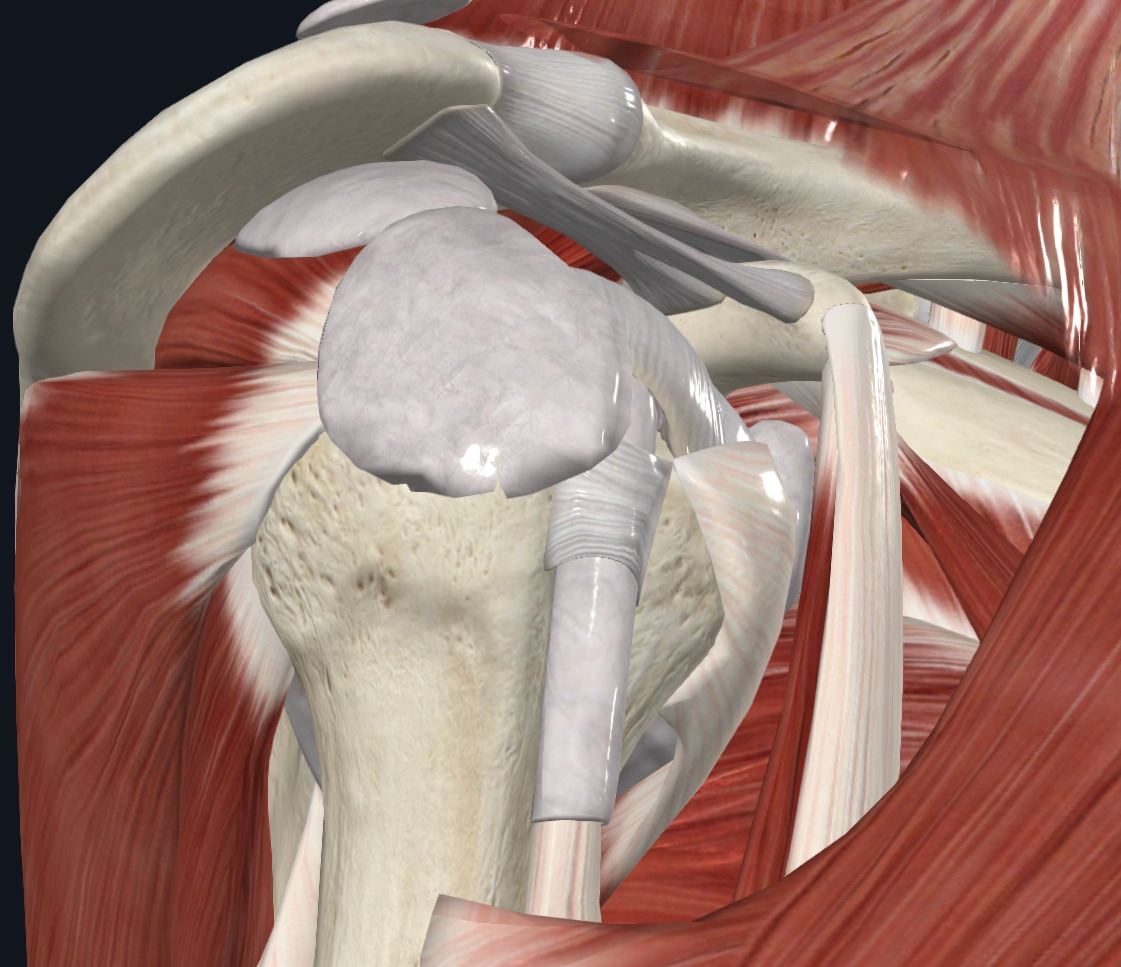

사진설명 - 어깨관절의 구조물을 보여주고 있다.

관절 속에 음압력을 구조는 힘줄, 인대, 관절와 등등이 존재하는데 우리가 능동적인 조절이 가능한 것은 근육이다.